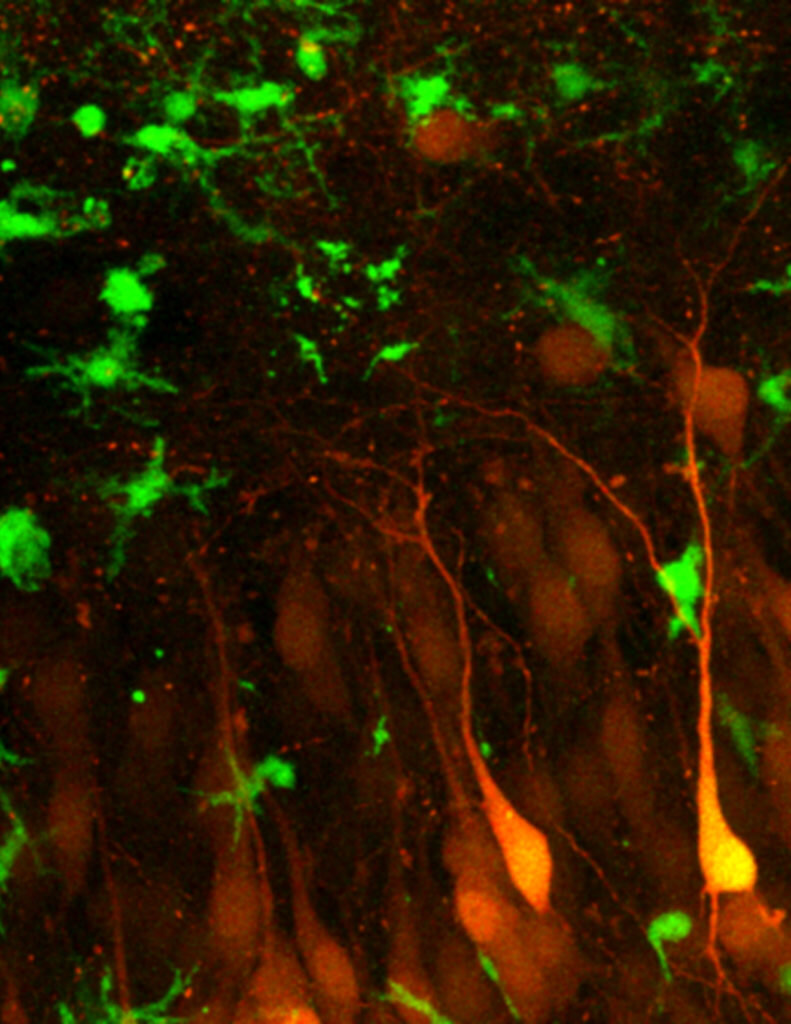

Картинка дня: нейроны гиппокампа и активированная микроглия

На этой прекрасной микрофотографии, сделанной в Университете Айовы мы видим нейроны гиппокампа (жёлтый) и активированные собственные иммунные клетки мозга — микроглию. О том, что такое микроглия, зачем она активируется и какие ещё функции выполняет, вы можете прочитать в нашей специальной статьецикла «Нейронауки для всех. Детали».